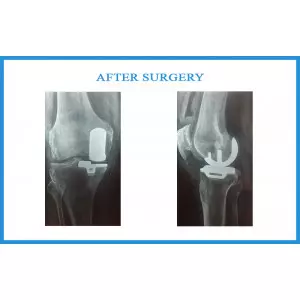

Bhagubhai Parikh